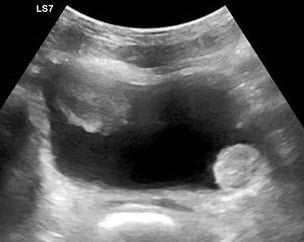

- The primary sonographic abnormality you will identify in the patient with suspected renal colic is hydronephrosis. The degree of hydronephrosis relates to the degree and extent of obstruction: (Illustration 2, Videos 11-17)

- After complete obstruction to flow, there is an acute rise in intrarenal pressure. The renal pelvis and calyces dilate first. On US you will see echo-free areas distending the normal bright (echogenic) central area of the kidney.

- As obstruction continues, the renal parenchyma becomes compressed and you see thinning of the pyramids.

- Illustration 2. Overview of degrees of hydronephrosis

- Simple or complex renal cysts- peripheral, smooth, hypoechoic and with or without internal echoes

- Renal cysts can sometimes be mistaken for hydronephrosis. Cysts are typically single and arise in the periphery of the kidney but can be multiple as in polycystic kidney disease.